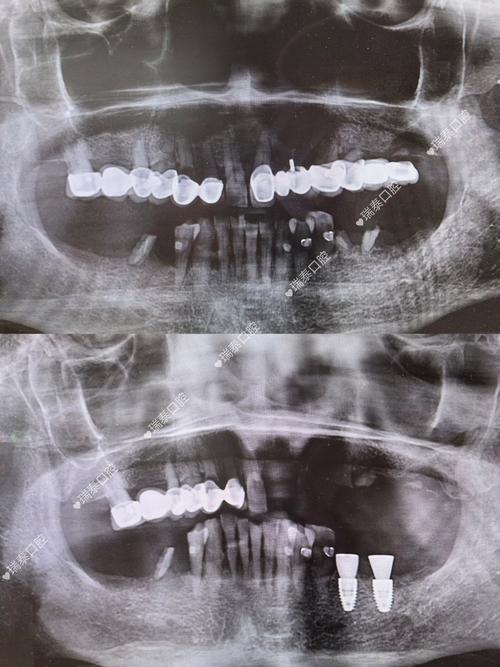

种植牙的成功,离不开精准的影像检查,现代口腔种植常用的影像技术包括根尖片、曲面断层片及锥形束CT(CBCT),其中CBCT因三维成像、高分辨率、辐射剂量可控等优势,已成为种植术前的“金标准”,拍片的核心作用体现在以下方面:

精确测量骨量,制定安全植入方案

CBCT可三维重建牙槽骨形态,清晰显示骨的高度、宽度、密度,以及骨内凹陷、缺损区域,医生通过软件分析,可精确计算种植体的直径、长度,选择合适的种植体型号,确保种植体植入后周围有至少1-2mm的骨壁包裹,提供初期稳定性,对于牙槽骨严重萎缩的患者,可通过CBCT判断是否需要植骨、骨增量手术的量及范围,避免盲目种植。

定位重要解剖结构,规避手术风险

CBCT能清晰显示下牙槽神经管、上颌窦底、颏孔、鼻腭管等解剖结构的位置及走行,下颌后牙区的种植体需距离下牙槽神经管至少2mm,上颌后牙区的种植体需距离上颌窦底至少1mm,CBCT可帮助医生精准标记安全植入范围,避免神经损伤和上颌窦穿孔,对于邻牙牙根倾斜、弯曲的情况,CBCT可明确牙根形态,确保种植体与牙根间保持足够距离(至少1.5mm)。

评估全身及口腔整体状况,排除种植禁忌症

拍片不仅是局部检查,还可结合患者全身情况(如是否有糖尿病、骨质疏松症等)及口腔整体健康(如是否有根尖炎症、囊肿、埋伏牙等)综合评估种植可行性,CBCT可发现牙槽骨内的囊肿或病变,需先治疗再种植;对于骨质疏松患者,可评估骨密度,调整种植体植入方案(如选择表面粗糙的种植体增强初期稳定性)。